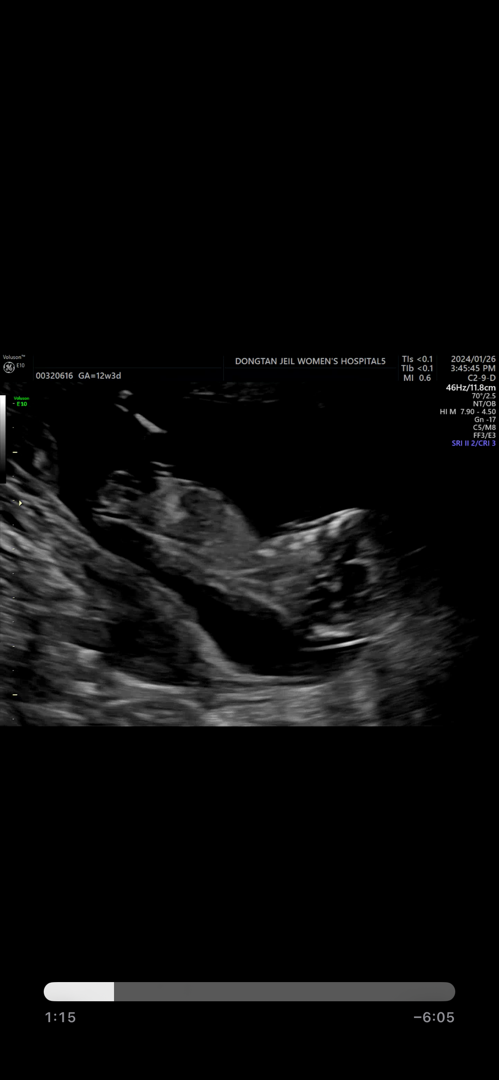

각도법 보이시나요???

혹시 보이시나여ㅠ 안보이네오ㅠㅠ안보이는게 맞죠? 유추 불가능 사진이겠져ㅜ